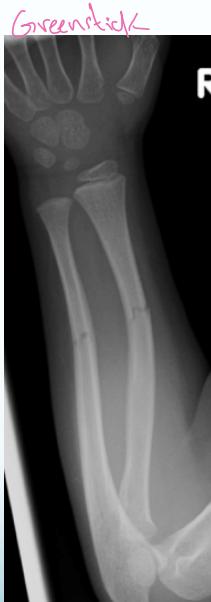

- Greenstick - only on cortex

- Plastic deformation - abnormal shape without fracture line